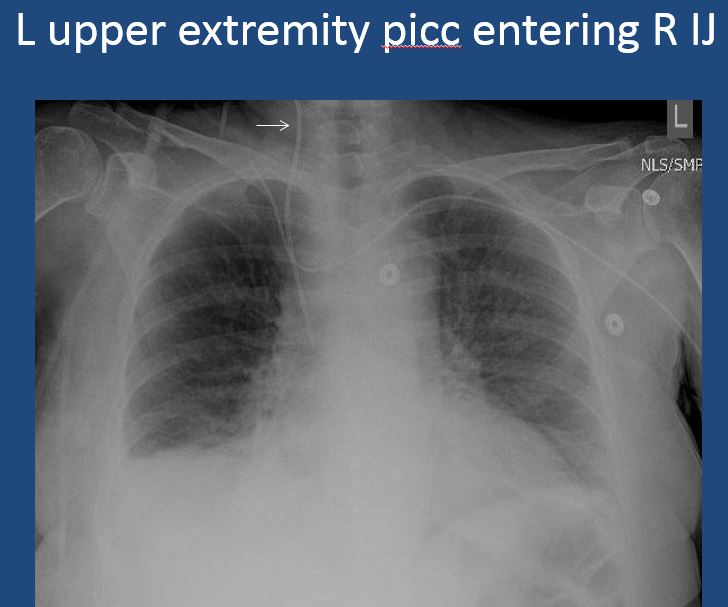

There is a venous line or lines present and in an improper location or otherwise abnormal. [Yes/No]